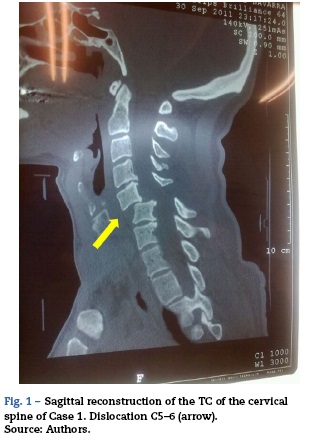

Case 1

A 44-year-old Caucasian woman, with no previous history of injuries, suffered a fall and was immobilized with a semirigid neck brace. Upon further exploration it proved to be a tetraparesis without other apparent injuries. The computerized tomography (CT) of the cervical spine showed a dislocation of C5 over C6 (Fig. 1). A surgical fix was chosen, so we explained it to the patient and obtained her consent for the anesthetic technique. Three hours after her admittance, in the operating room, after basic monitoring, we initiated a perfusion of remifentanil at 0.05 μgkg-1 min-1. We kept the neck brace on and initiated oxygen therapy through nasal prongs with capnography. We administered topical anesthesia to the patient with lidocaine aerosol at 10% into the oral cavity and the pharynx, encouraging the patient to gargle with the solution, ventilating her intermittently with a flexible tube. After 15 min we confirmed the anesthesia of the area, progressively introducing an oral catheter specifically for intubation with fiberoptic bronchoscopy. Through the catheter, we introduced a flexible fiberoptic bronchoscope, with a cuffed orotracheal tube (OTT) with an internal diameter of 7.5 mm, previously inserted. Once we could see the glottis we administered 3 mL of lidocaine at 2% through a flexible, single-tubed catheter introduced into the working channel of the fiberoptic bronchoscope. Next we advanced the catheter to the trachea and administered another 3 mL of lidocaine. The patient responded with a small, involuntary self-limited cough and we introduced the fibrescope until we reached the carina. Afterwards we advanced the OTT, rotating it 90°, which coincided with a deep spontaneous inhalation from the patient. The maneuver was performed without difficulty. After confirming the positioning of the OTT with capnography, we performed a new neurological examination that ruled out an aggravation of the patient's symptoms and we administered anesthesia with propofol and rocuronium. We carried out an anterior arthrode-sis without incident and the patient recovered without further injury.